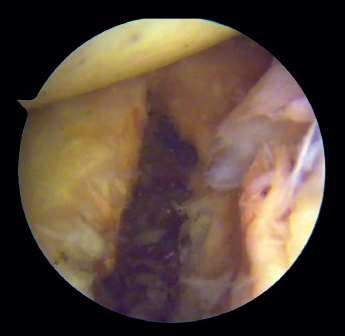

Introduction of the glenoid guide and positioning of the sheaths

(Figures 2 and 3)

Figure 2. View from the anterosuperior portal (left shoulder). Note the glenoid guide positioned at the centre of the defect and drilling at its upper and lower portion, spaced 10 mm apart.

Arthroscope is introduced through the anterosuperior portal, and the glenoid guide is introduced through the posterior portal, and passed paralel to the glenoid surface until the hook is located at the centre of the bone defect. The guide is secured with two cannulas inserted through two small accessory incisions, until connecting with the posterior cortical layer. Both cortical layers are drilled through them using a 2.8 mm drill fitted with a sheath so that on withdrawing the drill the sheath is positioned at drilling level. This step is made twice to introduce two sheaths: one above and the other below the glenoid guide hook and spaced 10 mm apart. Through these sheaths we advance two monofilament loops that are retrieved sequentially through the anterior portal for subsequent passing of the graft. At this point we can remove both sheaths and the glenoid guide, taking care to prevent the guide hook from coming into contact with the glenoid surface in order to avoid damaging to the cartilage.